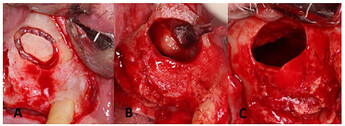

Lateral window preparation and the maxillary sinus cyst removal: (A ) lateral window preparation with Piezo surgery; the bony island was detached and saved in saline; (B ) sinus membrane after elevation and identification of the antral pseudocyst; (C ) sinus membrane perforation after specimen removal.